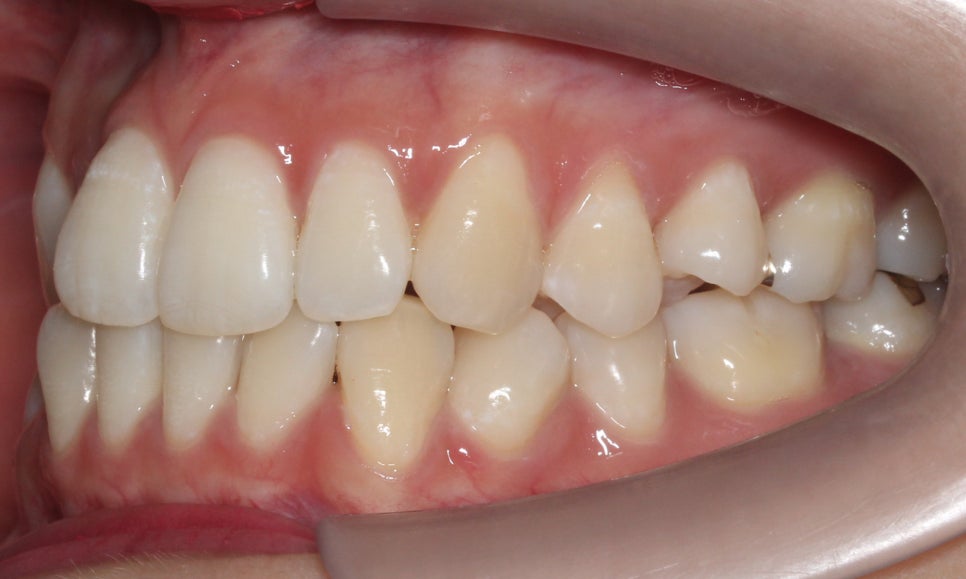

신논현치과 환자분의 교정 후 overjet 사진입니다.

교정 전에도 전치부의 돌출감은 그다지

심하지는 않았지만 교정 후 조금 더

가지런해지고 반대교합 증상을 보이던

측절치가 올바르게 교합되면서

전치부의 심미성이 보완된 모습입니다.

좌우의 교합 평면을 보면 협측의 치아 배열이

교정 전보다 가지런해진 것을 확인할 수 있는데요,

비발치로 교정을 진행하였기 때문에

전체적인 악궁의 길이는 짧아지지 않고

삐뚤어진 치아들만 바르게 배열된 모습입니다.

하악 또한 상악과 같이 전치부에서

발견되던 crowding이 사라졌고

치열이 가지런하게 바뀐 모습을 확인할 수 있는데요,